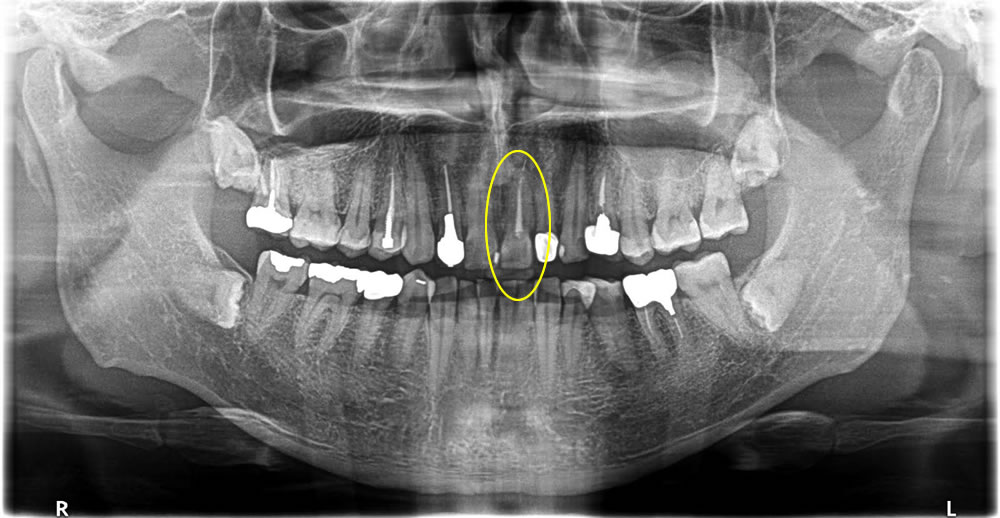

痛む前歯を抜歯後にインプラントで治療した症例

前歯が何もしなくても痛いと言う主訴で来院された患者さまです。検査をした結果、他院にて神経を取る治療を行った際に器具が破折し、歯の先端より外に飛び出てしまっていたので、治療方針を説明。当該歯を抜歯し、インプラントを希望されました。